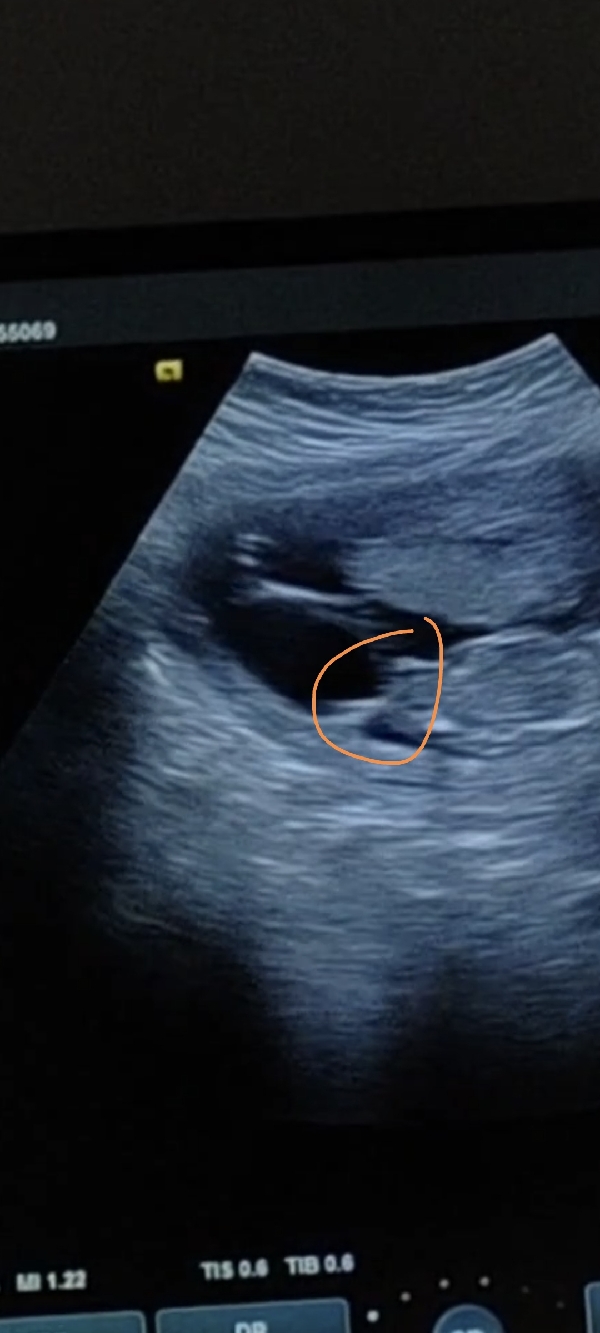

رحت للدكتورة بالأسبوع 14وقالت احتمال بنت لانه من تحت البيبي مو مبين حق ولد تقول مبين ٣ خطوط وعطتني موعد بعد اسبوعين تبغي تتأكد بس اني صورة فيديو ومبين كم لقطة من قدام و مفتوحة الرجل مادري تعرفون له لوو

اي هو مو مبين من تحت شي ولا في بروز وهاذي صورة من تحت مادري ليش قالت شاكة وبعد اسبوعين وبتتأكد قلت ليها اني بأول ولد ليي عطول بين عندي وعرفت انه ولد حتى قبل لاتقول الدكتورة يعني لو ولد مو معقولة مابيبين واني عندي ولدين